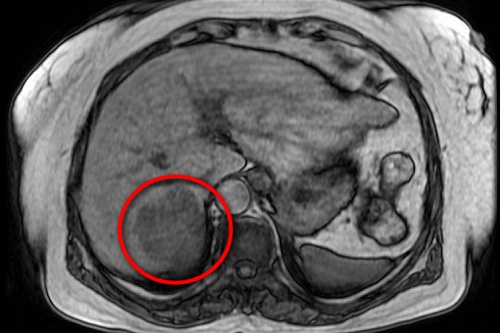

▲江阿嬤右肝7公分的肝腫瘤,經核磁共振等精密的檢查,證實為肝癌。

江阿嬤經由肝臟電腦斷層與核磁共振等精密的檢查,證實為肝癌,陳言丞主任說,因為阿嬤為高齡長者,若要手術得做詳細的檢查,確認她的心肺功能正常、生活能自理、走路也沒問題後,評估她可做積極的手術的治療,且為了降低對病人其他功能或其他的器官,包含心臟、肺臟、腎臟的影響,所以選擇以微創手術腹腔鏡來切除肝腫瘤,並在日前手術完整切除位於第7肝葉的肝癌腫瘤。